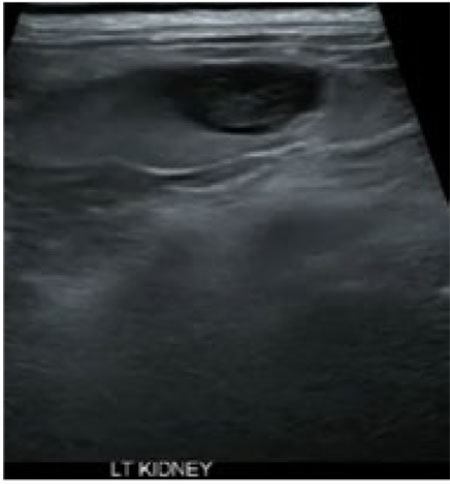

초음파 영상 상, 좌측 신장의 caudal pole에서 well-defined, round shape의 anechoic한 cystic lesions을 발견하였다. 환자의 혈액검사 및 요검사에서 특이사항은 발견하지 못하였다.